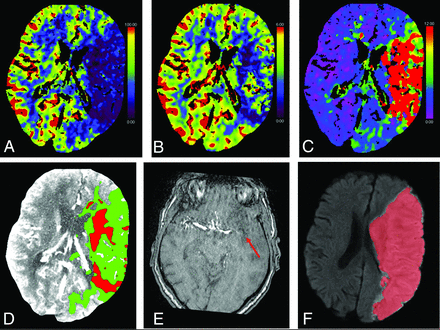

From 539 patients included in the MR CLEAN-NO IV trial, 228 had available CTP results. Of these 228 patients, follow-up imaging was performed in 145 patients, and they were included in our post hoc analysis. Eighty-one (56%) patients received IVT and EVT. Baseline characteristics such as age, sex, and baseline NIHSS were comparable for patients who received IVT and EVT versus patients who underwent EVT alone. Median baseline CTP-estimated ischemic core volume was 17 (interquartile range [IQR] = 4–35) mL versus 11 (IQR = 6–24) mL (P = .5). The median FIV was 13 (IQR = 4–48) mL versus 17 (IQR = 4–50) mL (P = 1.0). CTP ischemic core overestimation of >10 mL occurred in 17/81 (21%) versus 9/64 (14%) patients and occurred primarily in the white matter. The time between baseline CTP and follow-up imaging was comparable (27 versus 33 hours, P = .3). Good functional outcome occurred in 45/81 (56%) patients who received IVT and EVT versus in 37/64 (58%) patients who received EVT alone (OR = 0.86; 95% CI, 0.42–1.73; P = .7). Four (3%) patients showed early recanalization (ie, recanalization before EVT). Two patients with early recanalization received IVT before EVT. An example of a patient with a left-sided M1 occlusion and a baseline CTP-estimated core of 65 mL is shown in Fig 2. This patient underwent successful EVT alone (eTICI 3) with an onset-to-reperfusion time of 195 minutes. Follow-up CTA showed a visible calcified embolus in the left M1 (mAOL 0). Follow-up DWI showed substantial infarct growth (384 mL). See the Online Supplemental Data for a complete description of baseline, procedural, and outcome characteristics stratified per study subgroup.

Baseline CTP of a patient with a left-sided M1 occlusion with substantial infarct growth with complete reperfusion (eTICI 3) after 5 attempts within 195 minutes of onset. The collateral score at baseline CTA (not shown) was zero. The CBF, CBV, and time-to-maximum parameter maps are shown in panels A–C. D, Ischemic core (red) and penumbra (green) estimations. E, Follow-up MRA shows a re-occluded M1 with visible calcified embolus (red arrow, mAOL = 0). F, Follow-up DWI acquired at 15 hours after baseline imaging with FIV segmentation (red).